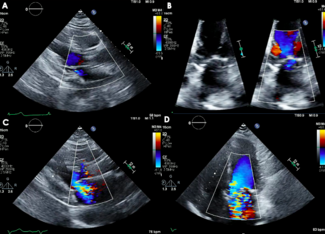

Clinical Images

04/15/2026

Matthew Atienza, MD; Ahmad Alkhalil, MD; Neda Dianati Maleki, MD; Jonathan Price, MD; Daniel Montellese, MD; Puja Parikh, MD

An 86-year-old man who had undergone recent transcatheter mitral valve-in-ring at an outside hospital presented with multiple hospitalizations for symptomatic hemolytic anemia requiring blood transfusions. Transesophageal echocardiogram...